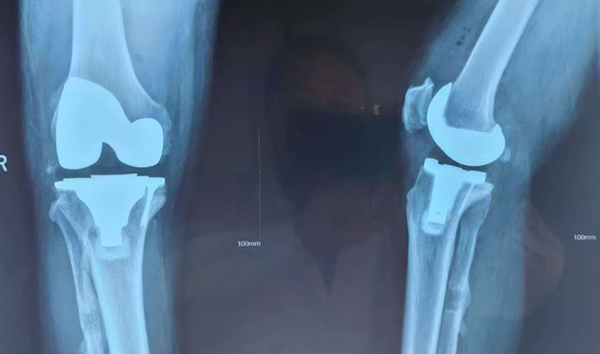

收入院后,骨科针对这名“忠实粉丝”进行术前讨论,患者右侧下肢膝关节严重内翻畸形,患者行走困难,因右腿为主力腿,术后不仅要依然达到主力腿效果,还需要达到身体平衡,这也提高了手术难度,且患者患侧膝关节内侧平台缺损3/5,本该应用平台垫块及延长杆,这样会给患者增加1万元的手术费用,为了提高患者的生活质量同时又不增加额外的经济负担,经骨科团队术前讨论决定将外侧平台增生的骨质切下后补在内侧平台缺损处,应用螺钉固定,纠正下肢力线 ,恢复膝关节平衡。

经过术前精心准备,手术如期进行,由经验丰富的彭明学主任医师亲自操刀,顺利为患者行右侧全膝关节置换手术,手术顺利,患者第3天就能下地行走,右腿依然是主力腿。

手术前X线照片

手术后复查X线照片